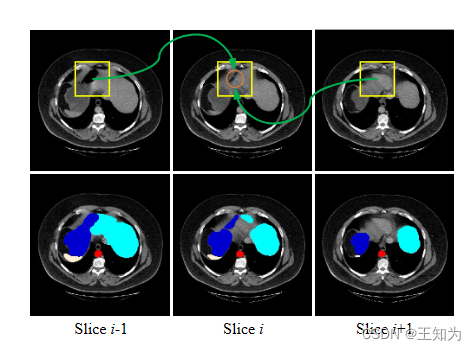

图1 这个图解释了切片间融合的原理。由于胃的内部类别方差很大(在深蓝色中标记),模型很难准确分类切片i上橙色的像素。通过引入切片间的信息,像素可以获得更丰富的上下文。